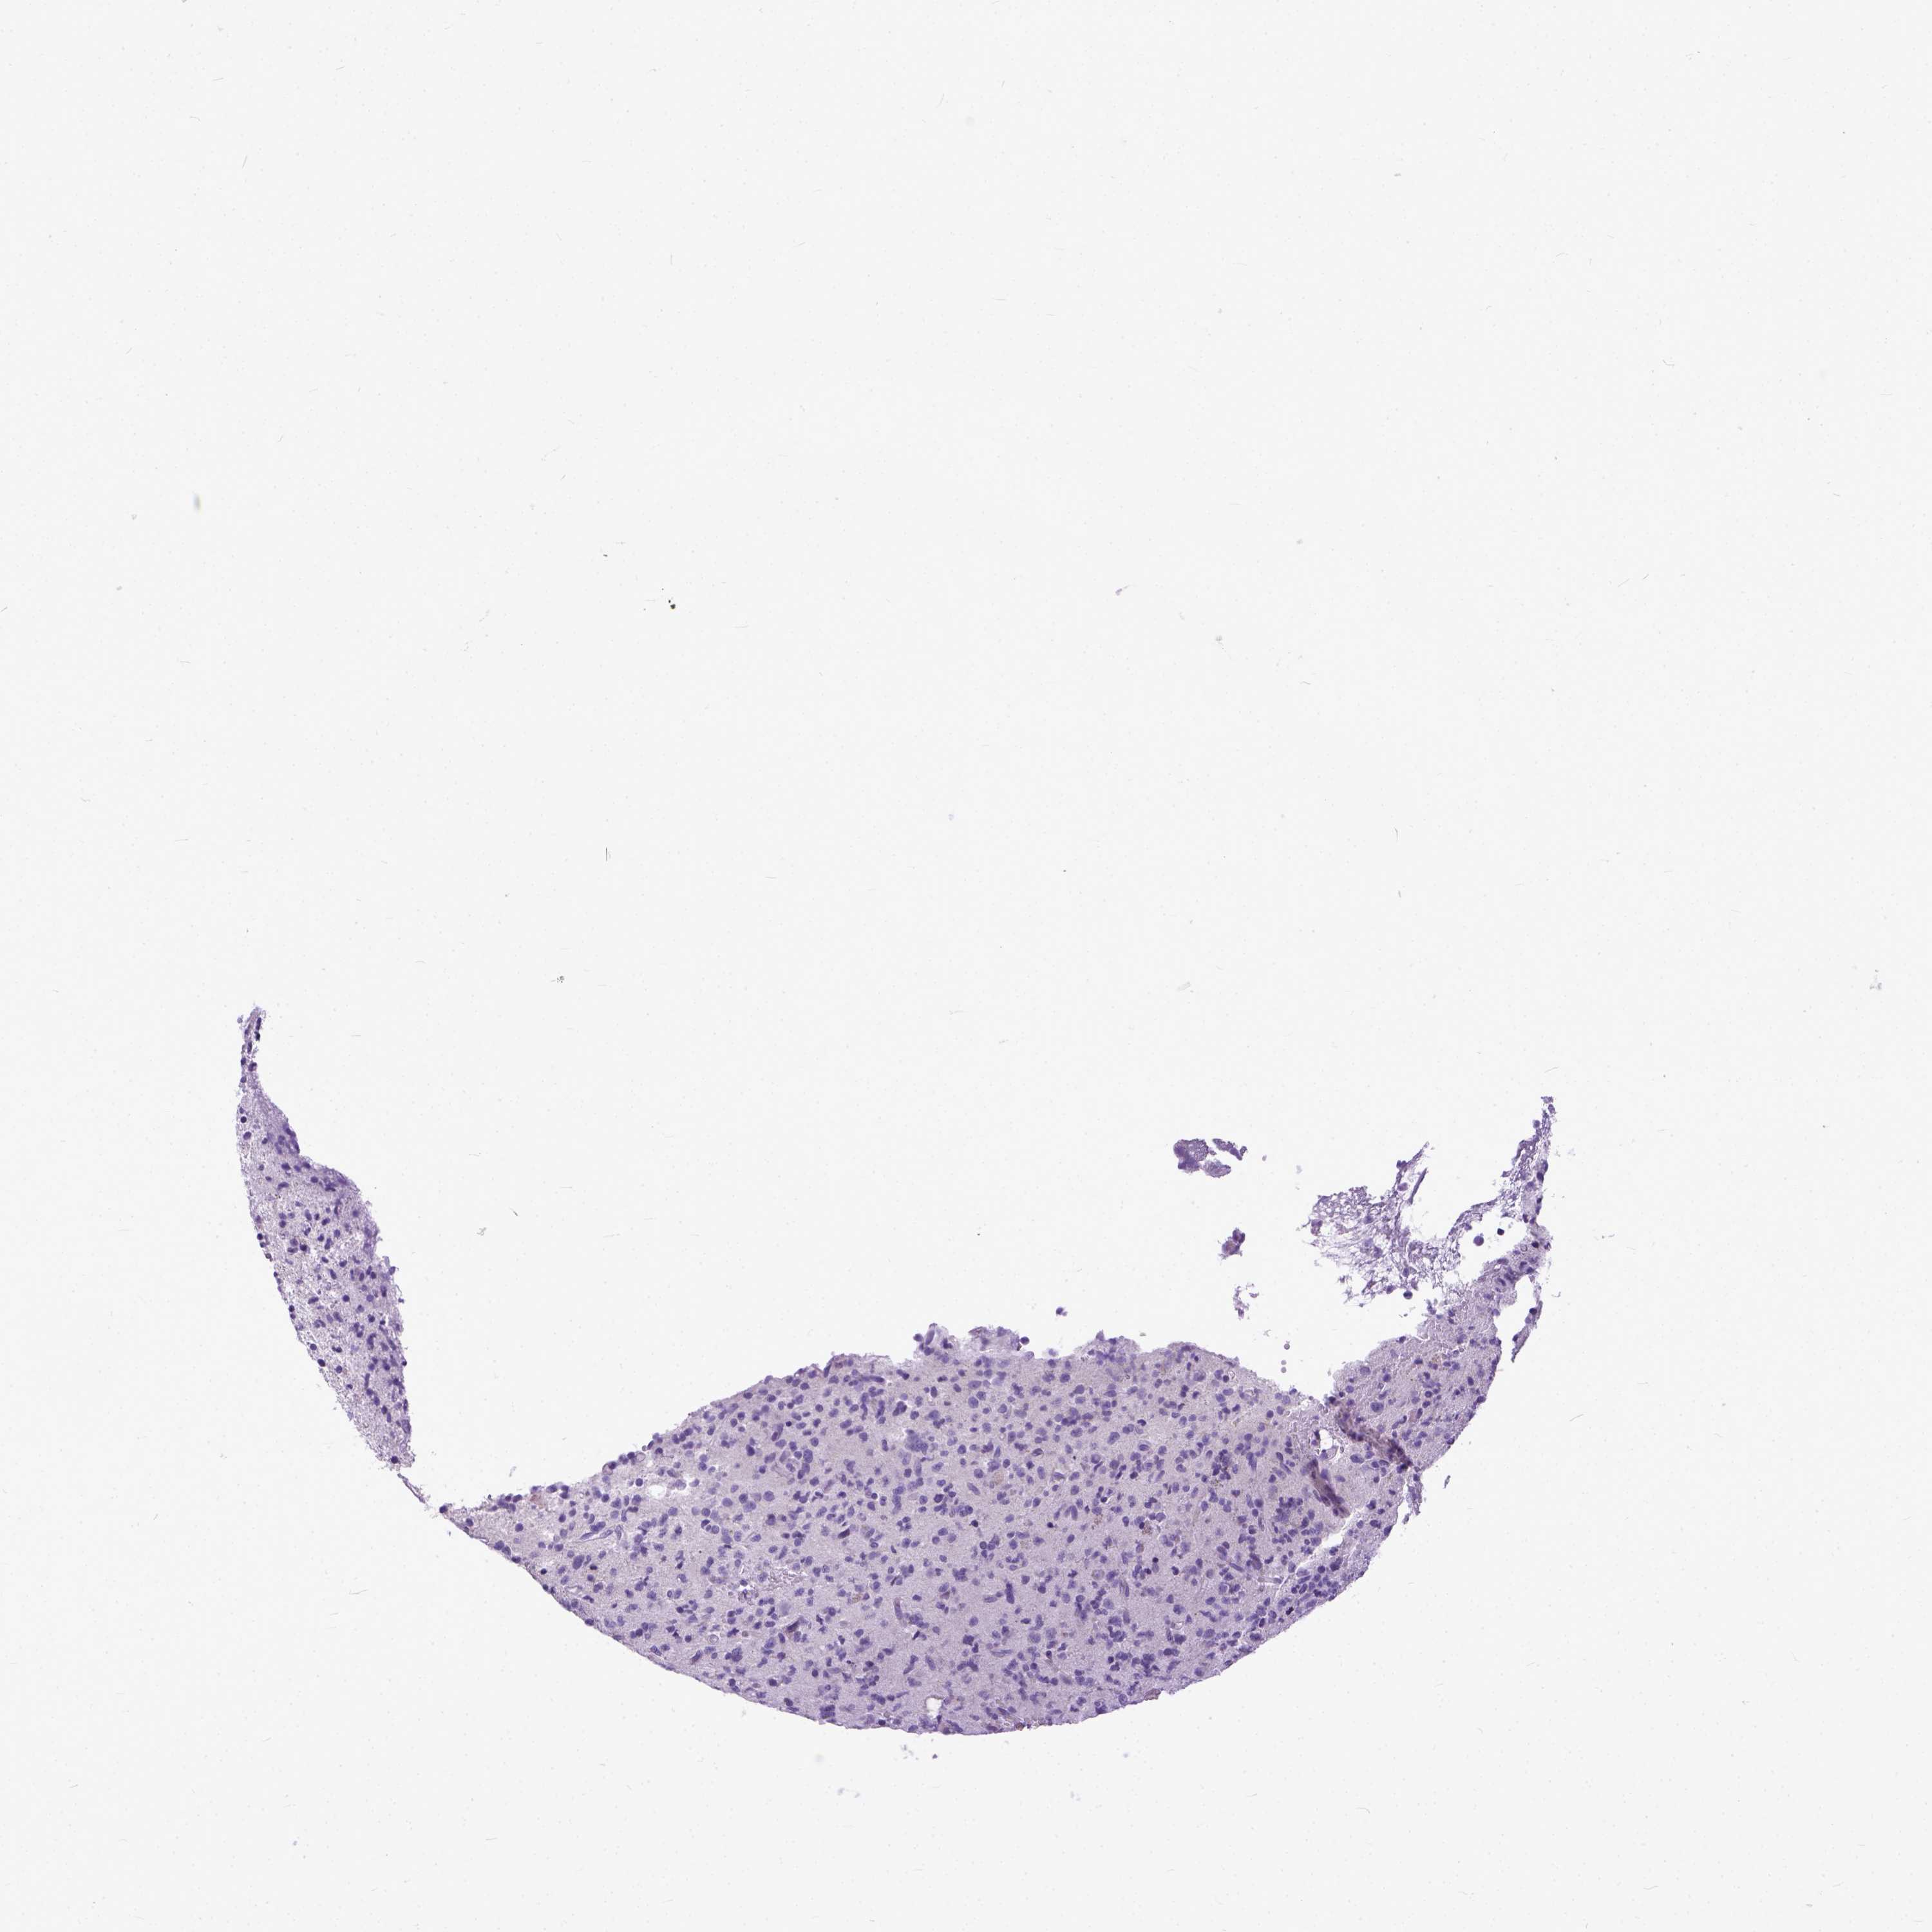

GLIOMA - Protein expressioni

A mouse-over function shows sample information and annotation data. Click on an image to view it in a full screen mode. Samples can be filtered based on level of antibody staining by selecting one or several of the following categories: high, medium, low and not detected. The assay and annotation is described here.

Note that samples used for immunohistochemistry by the Human Protein Atlas do not correspond to samples in the TCGA dataset.

Antibody stainingi

Antibody staining in the annotated cell types in the current human tissue is reported as not detected, low, medium, or high, based on conventional immunohistochemistry profiling in selected tissues. This score is based on the combination of the staining intensity and fraction of stained cells.

Each image is clickable and will lead to virtual microscopy that enables deeper exploration of all samples and also displays staining intensity scores, fraction scores and subcellular localization as well as patient and tissue information for each sample.

Antibody HPA035024

Staining

High

Medium

Low

Not detected

Intensity

Strong

Moderate

Weak

Negative

Quantity

>75%

75%-25%

<25%

None

Location

Nuclear

Cytoplasmic/membranous

Cytoplasmic/membranous,nuclear

Glioma, malignant, Low grade

Glioma, malignant, High grade